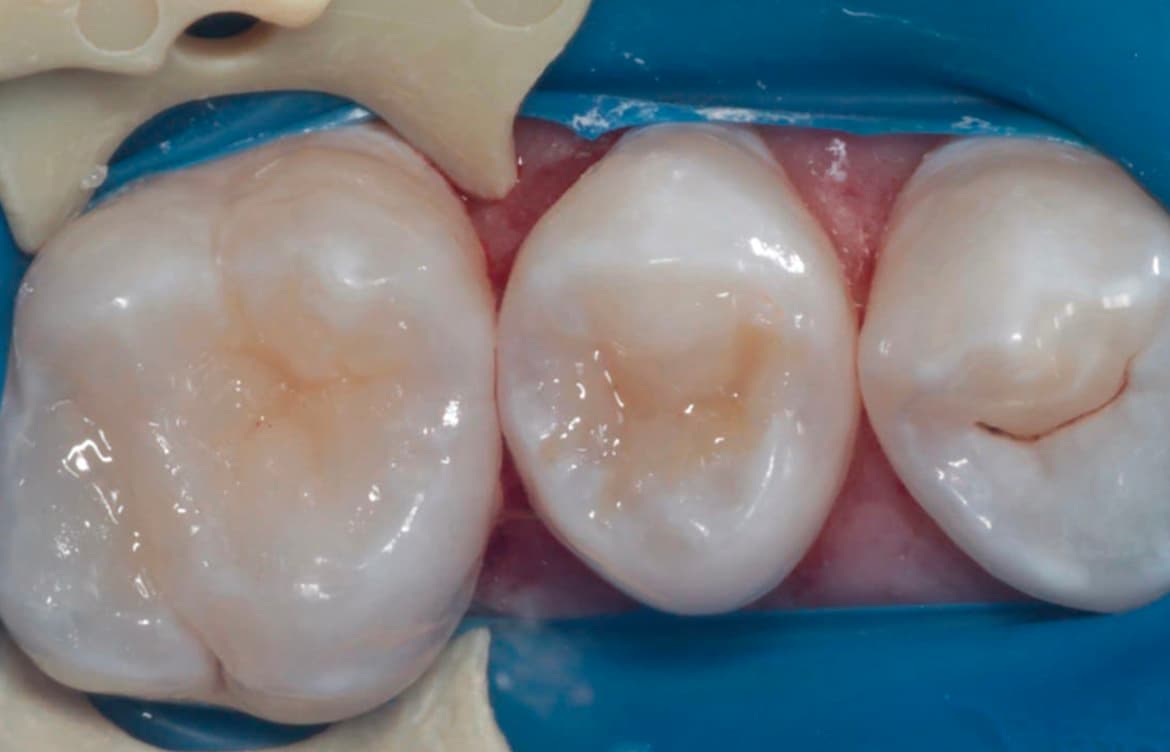

Минимальная инвазивность. Современные техники позволяют минимизировать травматичность хирургического вмешательства, сокращая период восстановления.

Использование биосовместимых материалов. Применение материалов, способствующих быстрому заживлению и регенерации тканей.

Наши работы